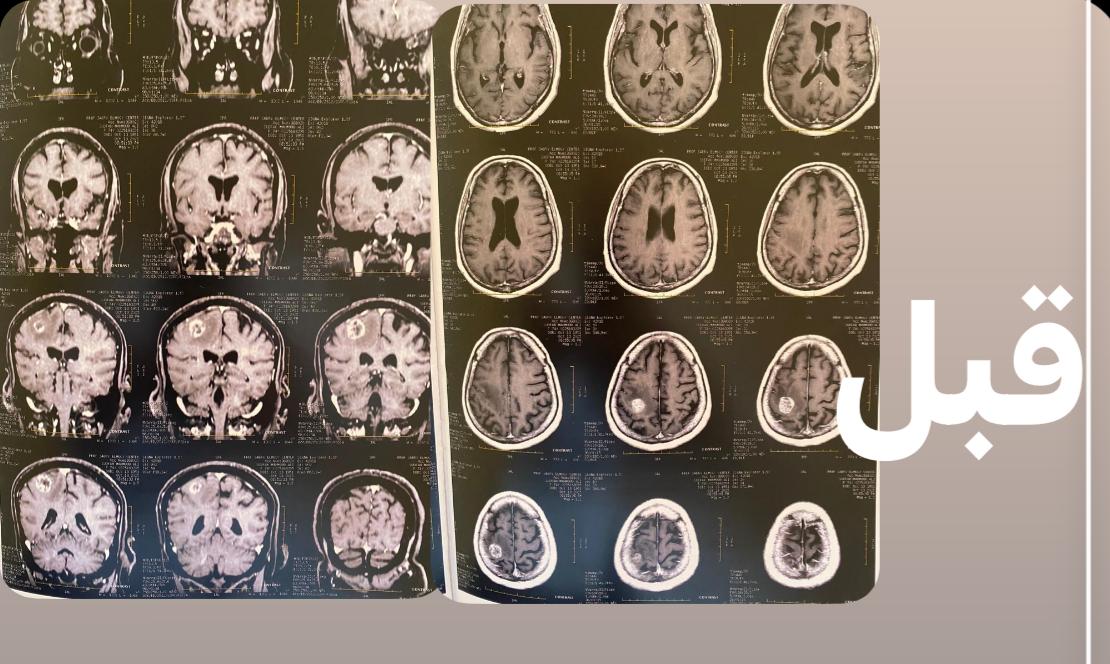

كانت المريضة حضرت إلى المستشفى وهي تعاني من تشنجات متكررة، وتدهور في درجة الوعي وشلل تام بالجانب الأيسر من الجسم، وبعد إجراء الأشعات والفحوصات اللازمة، تبين وجود ورم بالفص الأيمن للمخ يضغط على منطقة الحركة، مما تسبب في تلك الأعراض.

وأوضح الدكتور السيد فاروق، وكيل الطب العلاجي، أن الفريق الطبي بالمستشفى نجح، في استئصال الورم بالكامل من خلال جراحة دقيقة أجريت داخل المستشفى، مشيرًا إلى أن العملية تمت بنجاح كامل، وتحسنت حالة المريضة بعد الجراحة واستعادت وعيها الطبيعي وتوقفت التشنجات، وهي الآن تحت العلاج الدوائي والعلاج الطبيعي لحين تمام الشفاء.